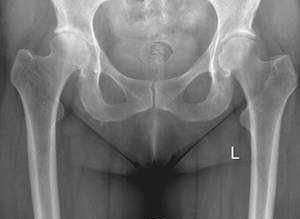

Die Arthrose verläuft also in verschiedenen Stadien, die gut auf dem Röntgenbild sichtbar und zu beurteilen sind, weshalb das Röntgenbild das wichtigste Diagnostikum bezüglich der Arthrose ist.

Während Ihres ersten Besuches bei uns in der Ambulanz wird durch das persönliche Gespräch mit dem Arzt, die körperliche Untersuchung und anhand der Röntgenaufnahmen das Stadium der Arthrose und Ihre persönliche Beeinträchtigung festgestellt. Bitte bringen Sie zu diesem Termin alle bereits durchgeführten Untersuchungen, alle Röntgen-, CT- oder MRT-Bilder, ggf. Arztbriefe bestehender Nebenerkrankungen oder einen etwaig vorhandenen Allergiepass etc. mit.